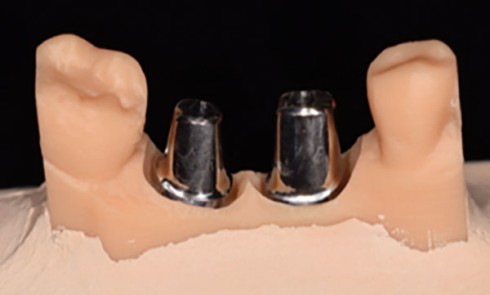

L’implant est devenu un outil incontournable de nos plans de traitement de réhabilitation orale. La codification des phases d’élaboration prothétique...